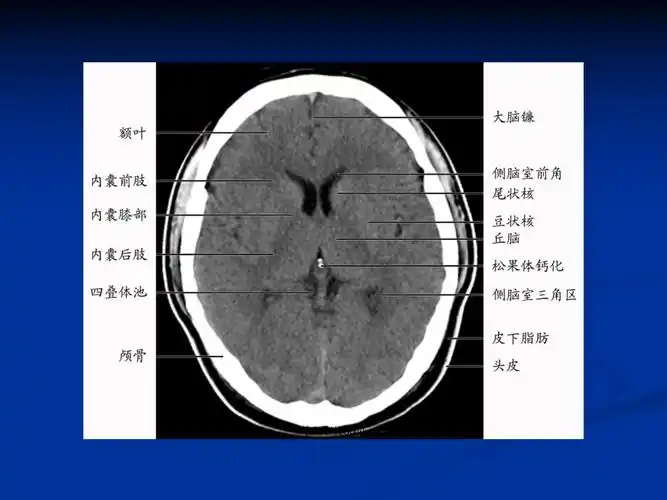

基底节区丘脑区对称性病变总结ppt教案